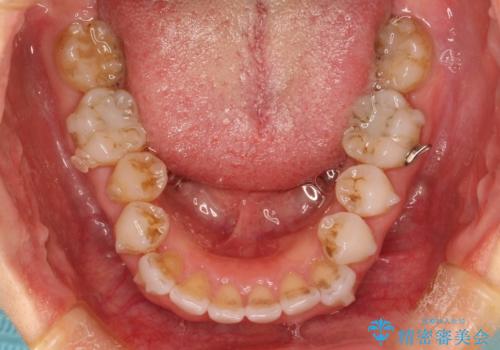

抜歯せずに八重歯のマウスピース矯正

- 非抜歯・遠心移動+IPR+拡大 によるマウスピース矯正を計画した。

八重歯がシビアな場合、抜歯をしないと治せないケースもありますが、奥歯の位置関係を修正したり、歯のサイズダウンを行うことで、抜歯をせずに改善できる場合もたくさんあります。